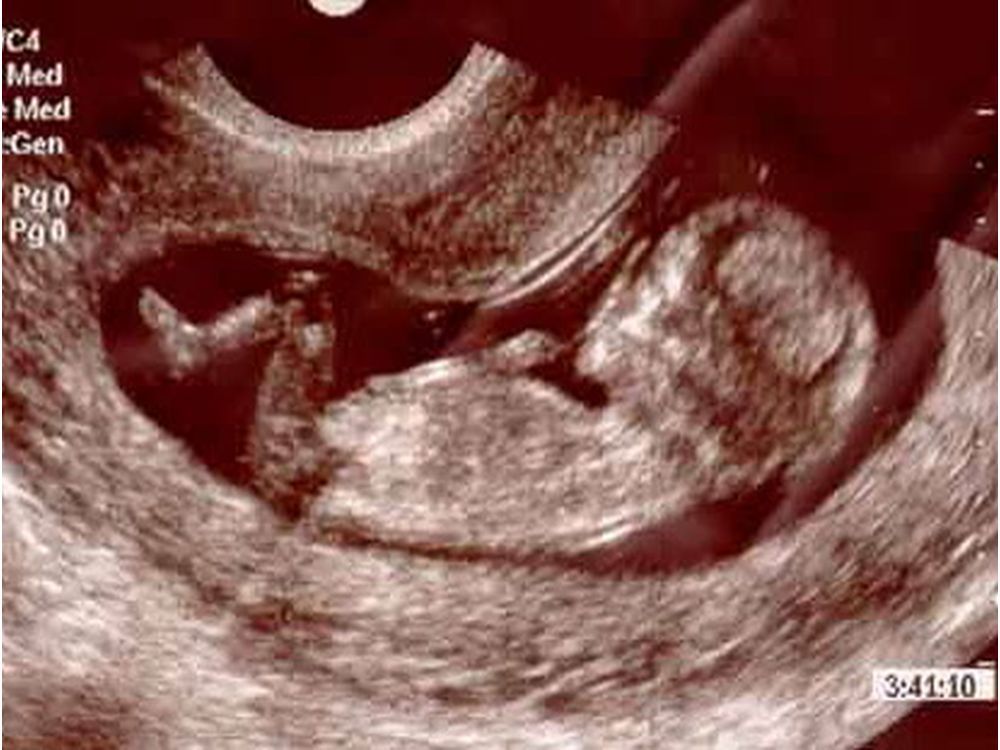

16 Акушерская Неделя Беременности Фото

16 Акушерская Неделя Беременности Фото 111 фото